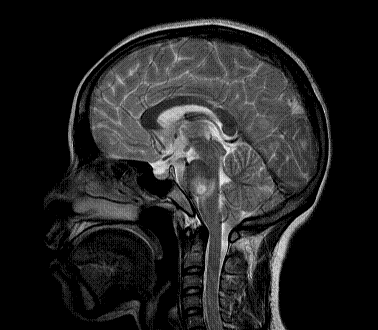

以下是引用xly在2009-5-20 11:38:00的发言:[br]大脑、小脑及脑干多发结节状及环状稍长t1、长t2异常信号影,部份病灶中心见稍短t1、短t2信号,病灶边缘光滑、边界清楚,灶周环状水肿,dwi为低信号,增强扫描上述病灶均匀强化,部份病灶中心无强化,脑膜小结节异常强化,考虑脑膜脑结核可能性大。胸片如何?ppd如何?期待结果。